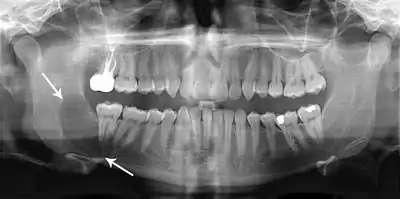

Classic look of an odontogenic keratocyst of the right mandible in the place of a former wisdom tooth. Well defined, unilocular, radiolucent lesion within the bone.

Diagnosis is usually radiological. However, definitive diagnosis is through biopsy. Aspirational biopsy of odontogenic keratocysts contains a greasy fluid which is pale in colour and contains keratotic squames.[11][2] Protein content of cyst fluid below 4g% is diagnostic of odontogenic keratocysts.[2] Smaller and unilocular lesions resembling other types of cysts may require a biopsy to confirm the diagnosis.[9] On a CT scan, the radiodensity of a keratocystic odontogenic tumour is about 30 Hounsfield units, which is about the same as ameloblastomas. However, ameloblastomas show more bone expansion and seldom show high density areas.[12]

Radiographs of odontogenic keratocysts show well-defined radiolucent areas with rounded or scalloped margins which are well demarcated.[11] These areas can be multilocular or unilocular. The growth pattern of the lesion is very characteristic from which a diagnosis can be made as there is growth and spread both forward and backward along the medullary cavity with little expansion. No resorption of teeth or inferior dental canal and minimal displacement of teeth is seen. Due to lack of expansion of the odontogenic keratocyst, the lesion can be very large when radiographically discovered.[9]